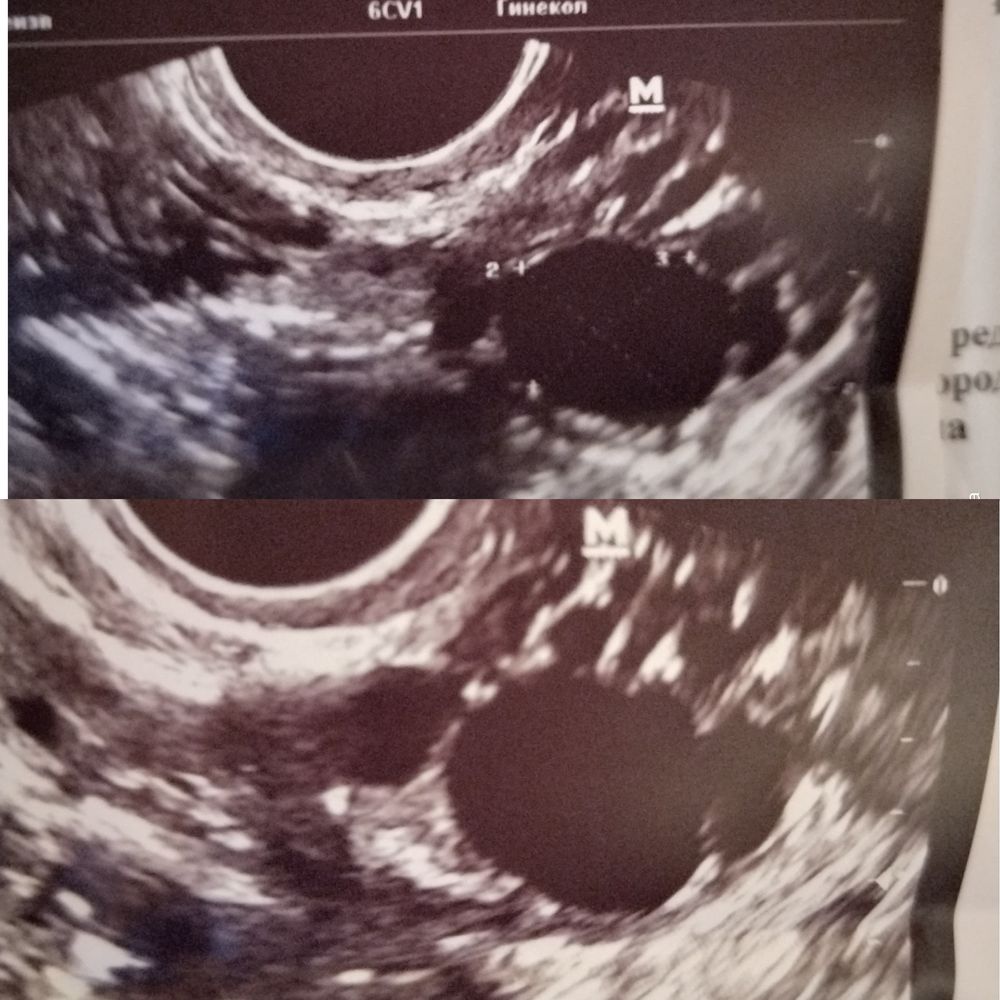

Девушки, добрый вечер🌼Сходила я на узи на 6дц и, вроде, всё не плохо, но есть вопросы)))

1) что такое дф с перегородкой(на фото)?

2) и если он с перегородкой, то дефектный и качественной О с жт и як не ждать от него? 🥺

Почему на 6 день цикла такой большой доминантный фолликул ? Это норма? Первый раз такое встречаю

Вот не могу утверждать, что у Вас такая же ситуация, но у меня как-то был такой же вариант с якобы перегородкой, потом смотрели по УЗИ и было два ЖТ. Качественной должна быть ЯК, а не фолликул. Вам бы стоило понаблюдать, когда я искала информацию по данному поводу, то многие подтверждали что бывает, что происходит двойная овуляция.

Латте, просто врач столько наговорила про этот дф. Типо он кистозный, но из-за размера кистой не назовешь пока. Потом, что с этой перегородкой. Почему-то из-за него поставила в диагнозе кистозный пя🤦♀️вот и думаю, может ли такой фолик норм як выпустить

Ирис_Ка, Я бы больше подумала, что это два разных фолликула, вот честно. И перепроверила бы такого врача. Иногда конечно бывает ранняя овуляция, на 9-10 дц, такое тоже может быть.